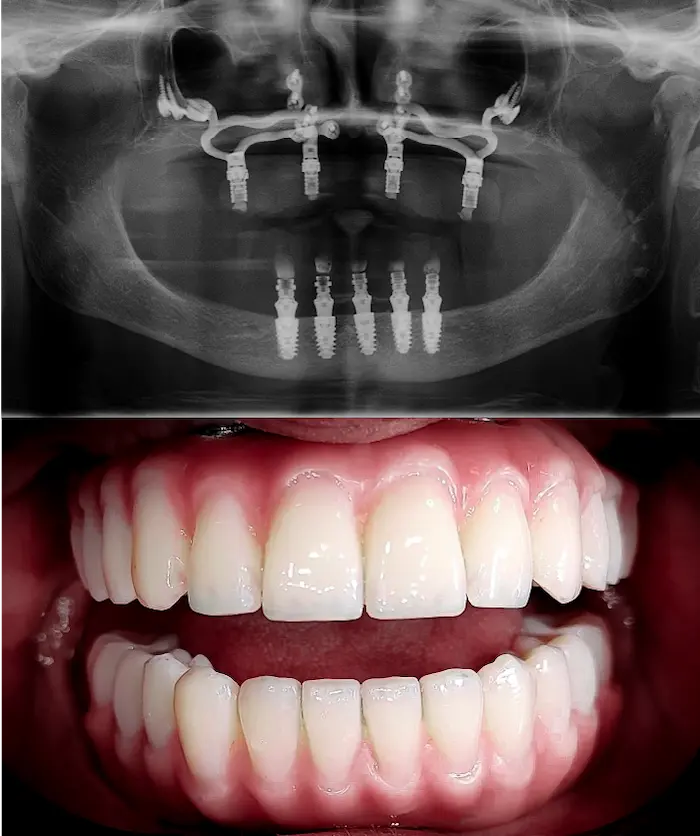

La soluzione di implantologia d’avanguardia quando non è possibile inserire impianti All-on o impianti zigomatici.

Gli impianti sottoperiostei (o impianti subperiostali) vengono creati su misura, in titanio puro T4 completamente biocompatibile, e applicati sulla superficie dell’osso residuo.

Sono progettati digitalmente per adattarsi alla tua anatomia in presenza di atrofia ossea severa.